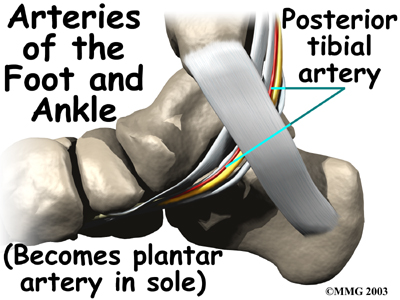

Blood Vessels

The ankle gets blood from nearby arteries that pass by the ankle on their way to the foot. The dorsalis pedis runs in front of the ankle to the top of the foot. (You can feel your pulse where this artery runs in the middle of the top of the foot.) Another large artery, called the , runs behind the medial malleolus. It sends smaller blood vessels to the inside edge of the ankle joint. Other less important from other directions also supply blood to the ankle.